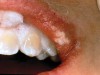

The whitening agents are available in various concentrations ranging from 10% carbamide peroxide (equal to 3.4% hydrogen peroxide) to 38% hydrogen peroxide. If the higher concentration agents contact the soft tissues, they can produce a chemical “burn” that turns the tissues temporarily white (Figure 1 and Figure 2). Although tissues quickly return to their normal color once they rehydrate, they may be mildly uncomfortable for a few hours. The patient may be distressed by the temporary appearance of the whitened soft tissues. A rubber dam or other protective barrier is mandatory to effectively seal off the tissues (Figure 3). In-office systems usually supply a light-cured resin in a syringe to apply around the cervical areas to confine the agent to the teeth (Figure 4 and Figure 5). In addition, flexible spreaders should be placed in the mouth to prevent the cheeks or lips from contacting the whitening agent.

Figure 2  Soft-tissue chemical burns near the left commissure of the mouth and along the free gingival margin due to exposure to the whitening agent.